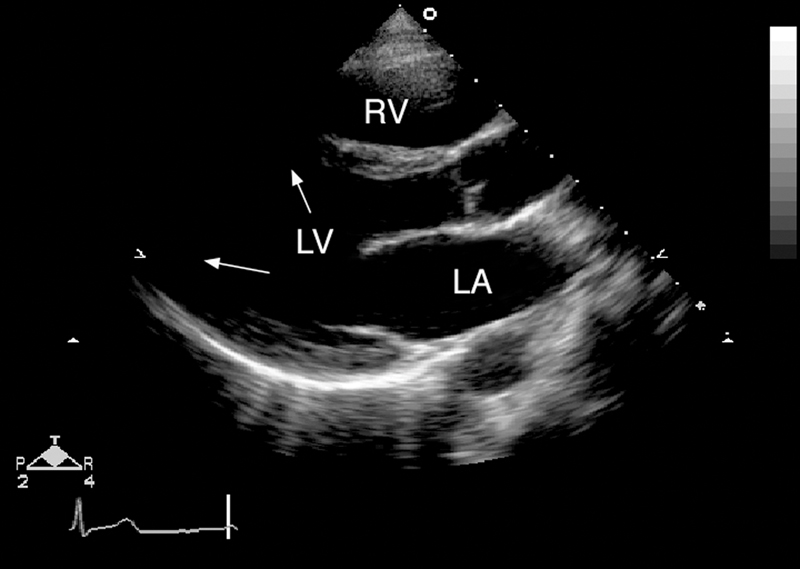

فحوصات تشخيصية لبعض امراض القلب والشرايين التاجية